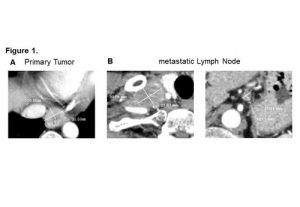

Lymphknoten können Überleben bei Patienten mit Ösophaguskarzinom vorhersagen1. August 2019 Illustration: © Sebastian Kaulitzki/Adobe Stock Forscher von der Graduate School of Medicine der Universität Osaka haben festgestellt, dass bei Patienten mit Speiseröhrenkrebs Lymphknoten zur Vorhersage von Rezidiven und des Überlebens eine größeren Nutzen haben als bisher verwendete Indikatoren. In der neuen Studie konnten die Autoren zeigen, dass im Vergleich zu Primärtumoren, die häufig zur Beurteilung der Behandlungsergebnisse bei vielen Krebserkrankungen herangezogen werden, die Reaktion der Lymphknoten auf eine neoadjuvante Chemotherapie (NACT) für die Vorhersage von Rezidiven und des Patientenüberlebens beim Ösophaguskarzinom effektiver ist. Zwar werden bildgebende Verfahren wie die Computertomographie (CT) und Endoskopie häufig zur Untersuchung von Primärtumoren bei Krebspatienten eingesetzt, doch sind sie bei der Messung von Primärtumoren in der Speiseröhre aufgrund ihrer Form nicht hilfreich. Daher ist es für Ärzte schwierig, das Risiko für Rezidive und das Überleben bei Patienten mit Ösophaguskarzinom abzuschätzen. Die Studienautoren versuchten, dieses Problem zu lösen, indem sie nach einem weiteren Indikator für das Outcome suchten. „Die Häufigkeit von Lymphknotenmetastasen ist besonders bei fortgeschrittenem Speiseröhrenkrebs im Vergleich zu anderen gastrointestinalen Tumoren sehr hoch“, sagen die Hauptautoren Shinya Urakawa und Tomoki Makino. „Infolgedessen schlussfolgerten wir, dass das Ansprechen von Lymphknoten für die Vorhersage der chemotherapeutischen Wirksamkeit und der Patientenprognose nützlicher sein könnte als das Ansprechen von Primärtumoren. Dementsprechend wollten wir den klinischen Nutzen des Ansprechens von Lymphknoten auf eine NACT für die Vorhersage des Langzeitüberlebens bei bestimmen Patienten mit metastasiertem Ösophaguskarzinom bestimmen.“ Zu diesem Zweck beurteilten die Forscher mittels CT von Metastasen betroffene Lymphknoten vor und nach einer NACT bei Personen mit metastasiertem Ösophaguskarzinom. Sie ermittelten das chemotherapeutische Ansprechen, indem sie die jeweilige Größe der Primärtumoren und aller metastasierten Lymphknoten überwachten, die bestimmte Kriterien erfüllten. Beurteilung des Ansprechens auf eine neoadjuvante Chemotherapie mittels Computertomographie. Die Fläche des Primärtumors wurde zweidimensional gemessen, basierend auf dem größten Durchmesser und der größten senkrechten Länge (A). Das Ansprechen der Lymphknoten wurde bewertet, indem die Nebenachsen aller positiven Lymphknoten gemessen wurden; die Summe wurde basierend auf RECIST-Kriterien (Response Evaluation Criteria in Solid Tumors) (B) berechnet. (Quelle: © Osaka University) „CT-Scans, die vor und nach NACT durchgeführt worden waren, zeigten eine hohe Nichtübereinstimmung zwischen Primärtumoren und von Metastasen betroffenen Lymphknoten bezüglich des Ansprechens“, berichtet Yuichiro Doki, Letztautor der Studie. Tatsächlich stellten die Forscher fest, dass jeder Lymphknoten eine andere Reaktion zeigte, auch bei ein und demselben Patienten. Daher halten die Wissenschaftler es für hilfreich, alle von Metastasen betroffenen Lymphknoten zu berücksichtigen, um eine genaue Einschätzung des Ansprechens auf eine NACT zu erhalten. „Das Ansprechen der Lymphknoten ermöglichte präzise Vorhersagen der Patientenprognose“, so Urakawa und Makino. Dieser Befund erleichtere nicht nur die Prognose der Outcomes, sondern könne auch zur Optimierung von Behandlungsstrategien beitragen und letztendlich das Überleben von Patienten mit metastasiertem Speiseröhrenkrebs verbessern.